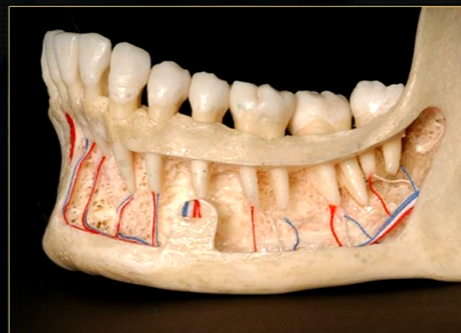

mandible varies in cross sectional thickness

left hand side of the mandible buccal surface has been removed

roots of the teeth protrude in the underlying trabecular bone

inferior dental nerve

mental nerve - coming out of the mental foramen

reveals honeycombed pattern of trabecular bone

dense outline of the individual sockets of the teeth

cortical bone which forms the lower border

periapical region

can see honeycombed pattern

mental foramen - black radiolucency - near 1st and 2nd premolars

sockets of the teeth are represented by thin, white, opaque lines → ‘ lamina dura’

dense, white, radiopaque line → dense bone of mylohyoid ridge

underneath mylohyoid ridge - looks more radiolucent → this is due to the lingual indentation of submandibular fossa

dense cortical bone of the lower border

radiolucent shadow created by the lingual pit